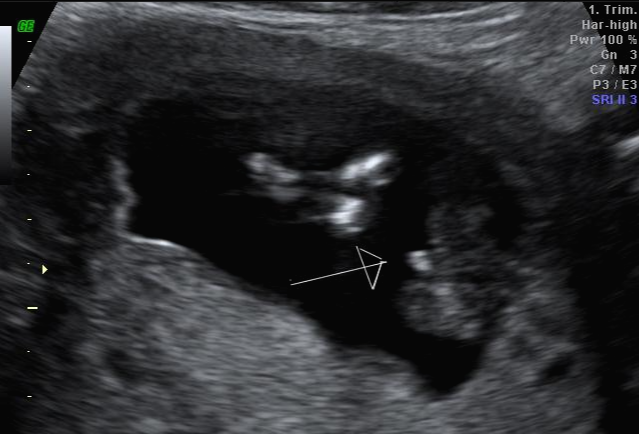

그리고 초음파 봐주시는 분께서 13주차가 되면 정확히 알 수 있으니 다음 주에 오라고 하셔서 일주일 뒤 다시 방문을 했습니다. (위에 사진은 12주 차 때 아들이라고 보여주신 초음파 사진이에요~ 화살표 보면 툭 튀어나와있는 부분을 보여주면서 아들이라고 하셨어요~)

아 진짜 전문가는 다르구나~ 이렇게 이른 주수에도 성별을 알 수가 있구나 생각을 했지만 이 시기 때는 성별을 정확히 알 수 없다는 글들을 봐서 살짝~ 의심스럽기도 했지만 그래도 100프로라니깐 ㅎㅎ 믿어보았어요~ 근데 위에 사진을 보면 성별을 알 수 있는 각도 법이 있는데 각도가 딸 같아서 긴가민가~하긴 했지만 의심은 잠시! 전문가 분을 믿기로 ㅋㅋㅋㅋ